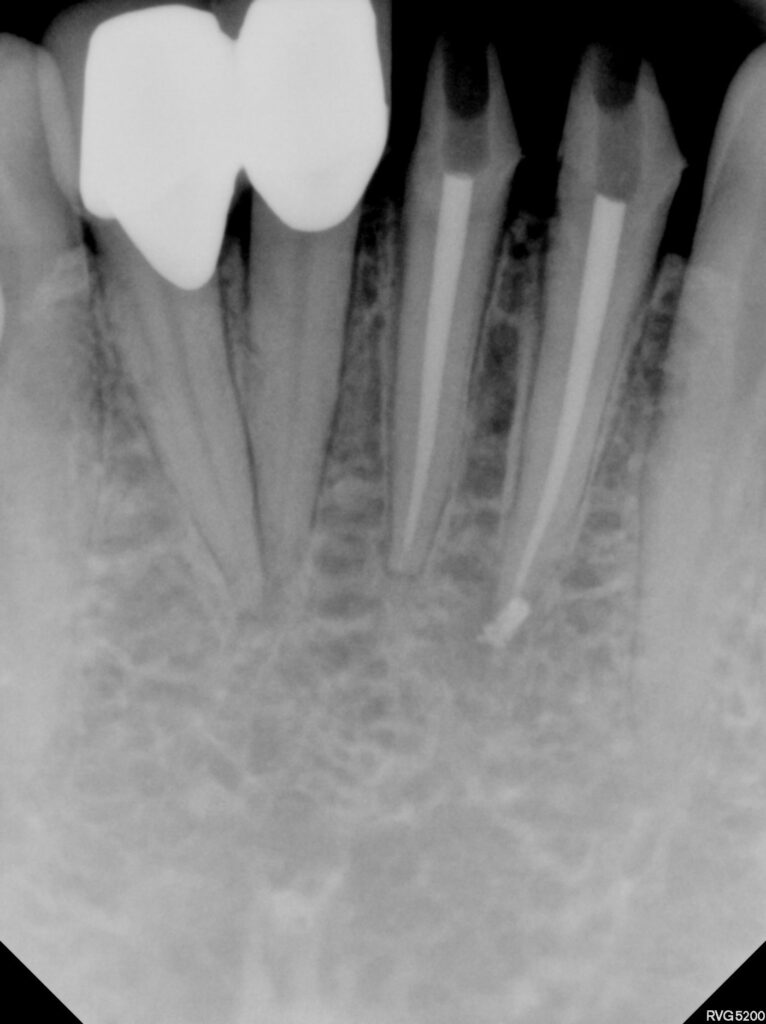

급성 치수염으로 인해 기존 보철물을 제거하고

신경치료가 필요한 상황이었는데요.

4개의 치아 중 문제가 있는 치아를 감별하기 위해

러버댐으로 치아를 격리하고 ICE / Hot test 시행하여

감별진단하였습니다.

처음 내원 시 마취도 잘 되지 않을 정도의

심한 치수염 상태였으나 신경치료를 한번

진행하고 난 후에는 통상적인 과정으로

진행할 수 있었습니다.

이를 해결해내기 위해 결국 4개 치아

모두 신경치료 후 크라운을 싱글로 제작하였습니다.